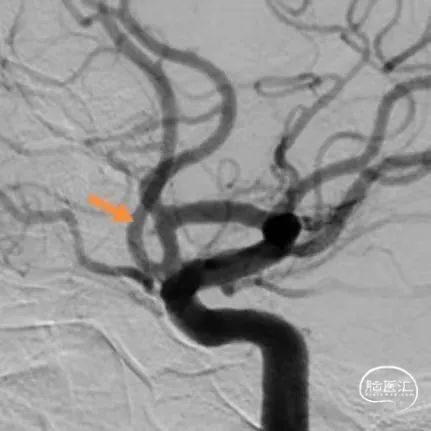

术后即刻影像

术者体会

Experience

左侧大脑中动脉分叉部动脉瘤呈分叶状,有子瘤,破裂风险大,累及大脑中动脉上下干,且动脉瘤形态不规则,需分区填塞。填塞使用的Jasper®SS弹簧圈圈体柔软,在瘤内钻缝能力强,能够很好地达到填塞效果,柔软性能强,基本不踢管,电解脱快速顺利,增加了手术的安全性及成功率。